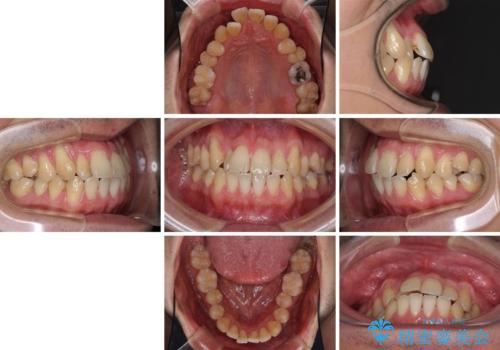

- 上下の前歯の反対咬合を気にして来院された患者様です。

インビザラインを用い、下顎はIPR(歯と歯の間を削る)と歯列全体を後方に移動させ、上顎は前歯を持ち上げることで、反対咬合を改善していくこととしました。

八重歯の歯根が見えている点も気になっているので、矯正歯科治療後に歯肉移植による根面被覆を行うこととしました。

インビザラインによる反対咬合の改善は、上の歯が下の歯を乗り越えていく期間に咬み合わせが非常に不安定となり、治療が長期化することがあります。

また、ワイヤー矯正と異なり歯軸改善の強い力を前歯にかけるため、反対咬合で裏側にある歯の歯肉が退縮しやすくなります。

矯正治療により元々気になっていた八重歯と、反対咬合が改善された歯の2本に対して根面被覆を行い、審美面の改善も達成しました。